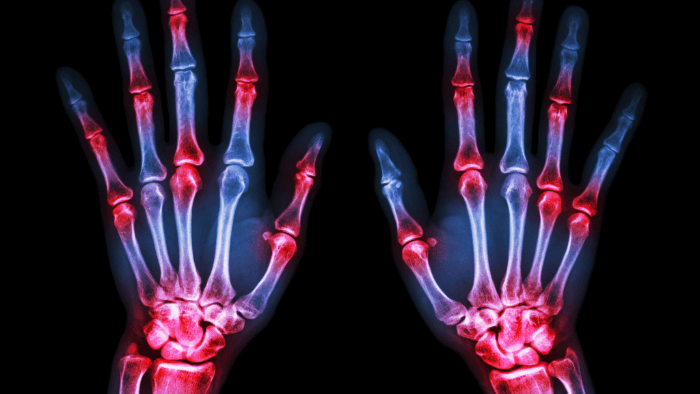

What is Arthritis?

x-ray of two hands with red spots over the joints indicating arthritis

At its core, arthritis is a term that simply means inflammation of the joints, but that definition doesn’t quite capture how complex or varied it really is. There are over 100 different types of arthritis, each with its own triggers, symptoms, and long-term consequences. (12) Some forms are purely mechanical, while others are driven by immune dysfunction. Some come on slowly and quietly over the years, and others seem to appear overnight. What they all have in common is this, they compromise your joints.

Here’s how arthritis shows up in most people (13, 14):

• Joint pain and stiffness, especially after periods of rest due to decreased lubrication

• Swelling or warmth around the joints

• Reduced range of motion or joint deformities

• Difficulty with movement, walking, or daily tasks

• In more aggressive types, fatigue and systemic inflammation

Recognizing Rheumatoid Arthritis

RA is notorious for being sneaky in its early stages. It might feel like a bad flu or vague joint pain at first. But it usually becomes more distinct over time.

Here’s what to watch for (42):

• Symmetrical joint pain: Unlike OA, RA typically affects joints on both sides of the body (e.g. both wrists or both knees).

• Morning stiffness lasting longer than 30–60 minutes

• Swollen, warm, and tender joints: especially in the fingers, wrists, elbows, and knees.

• Fatigue, low-grade fever, weight loss: systemic inflammation affects the whole body.

• Progressive joint deformities: like ulnar deviation in the hands or joint subluxations.

• Flare-ups and remissions: Symptoms can worsen suddenly and then calm down for a while.

RA can appear at any age, though it most commonly shows up between ages 30 and 60. (42) Women are affected about three times more often than men.